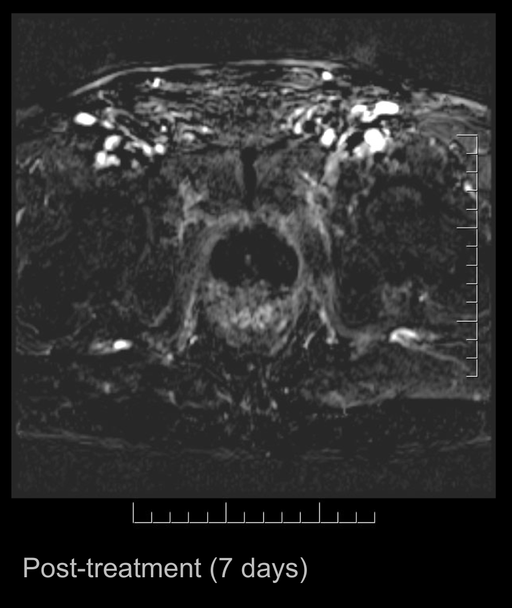

The company has previously announced that the last treated patient prior to treatment had a PSA value of 4.9 ng/ml and, upon revisiting after treatment, the value had fallen to 0.3 ng/ml, indicating that the cancer tumour was eradicated. At the lecture, Johannes Swartling showed images from the MRI scans that were made before and after treatment. These MRI images in combination with the measured changes in the PSA value represent a clear indication that the tumour has been eradicated and that the treatment has achived the intended effect.

The images are appended with this press release.